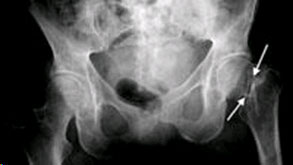

The diagnosis of a hip fracture is generally made by an X-ray of the pelvis and the affected hip and femur. Hip fractures occur at the upper end of the thigh bone (femur). In some cases, if the pa-tient falls and complains of hip pain, an incomplete fracture may not be seen on a regular X-ray. In that case, magnetic resonance imaging MRI or CT scan may be recommended. An MRI may identi-fy a hip fracture otherwise missed on plain X-ray. If the patient is unable to hae an MRI scan be-cause of an associated medical condition, computed tomography (CT) may be obtained instead.

In general, there are three different types of hip fractures. The type of fracture depends on what ar-ea of the upper femur is involved and are classified as intracapsular, intertrochanteric and sub-trochanteric fractures

This fracture occurs between the neck of the femur and a lower bony prominence called the lesser trochanter. The lesser trochanter is an attachment point for major muscles of the hip. The greater trochanter is the bump you can feel under the skin on the outside of the hip. It acts as another mus-cle attachment point. Intertrochanteric fractures generally cross in the area between the lesser tro-chanter and the greater trochanter. A typical inter-trochanteric fracture line runs between the greater and the lesser trochanter of the femur. It may further be sub-classified into various subtypes based on the number of fracture fragments and the fracture pattern